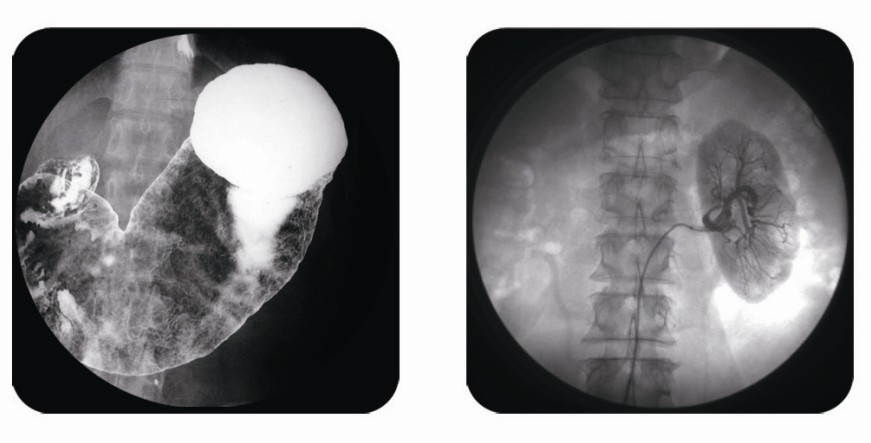

傳統(tǒng)胃腸造影檢查,病變顯示率低,輻射劑量大。普朗醫(yī)療器械公司生產(chǎn)的幾款多功能腸胃造影x光機,更能滿足不同等級不同規(guī)模的大小醫(yī)院選擇,從臨床及科研都很好。尤其最新的PLD8800多功能腸胃造影x光機用途更為廣泛。多功能腸胃造影x光機是目前各大醫(yī)院最普及的且用途最廣的一種X光機。普朗醫(yī)療的胃腸機功能多,簡便易用,能保證圖像質(zhì)量,該機采用高制式電視系統(tǒng),優(yōu)秀的數(shù)字化系統(tǒng)能使多功能腸胃造影x光機的性能得到提高,應(yīng)用范圍獲得極大的拓寬。

2、特殊檢查的應(yīng)用:如“T”管造影、消化道鋇餐、靜脈腎盂造影、子宮輸卵管碘油造影等,在實時監(jiān)視的同時隨時采集,抓住關(guān)鍵圖像,并可連續(xù)采集,電影回放整個過程。

3、介入方面的應(yīng)用:能很好開展全身各部位的血管造影、藥物灌注、栓塞治療及經(jīng)皮穿刺活檢引流,主要應(yīng)用于血管造影診斷及腫瘤的治療,不明原因腫塊的性質(zhì)確定。